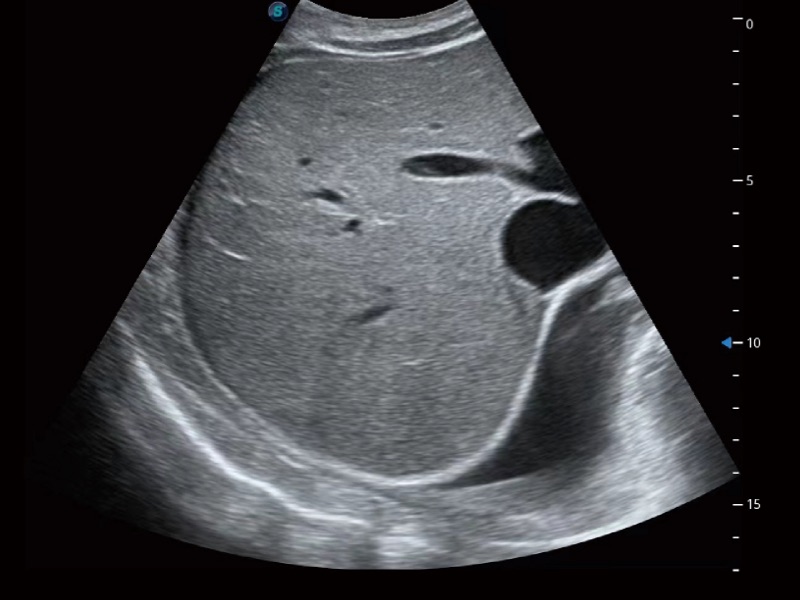

• SR Flow 高分辨率血流成像技术

高分辨率血流成像技术提高了对低速血流信号的检测能力。在提高空间分辨率的同时,也克服了血流外溢现象,为用户提供更加真实的血流动力学信息。

临床图